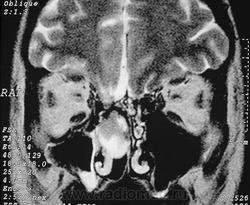

Фронтоэтмоидальное энцефалоцеле.

Отдел патологии, школа медицинских наук.

Государственного Университета Кампинас (UNICAMP).

Кампинас, Сан-Паулу, Бразилия.